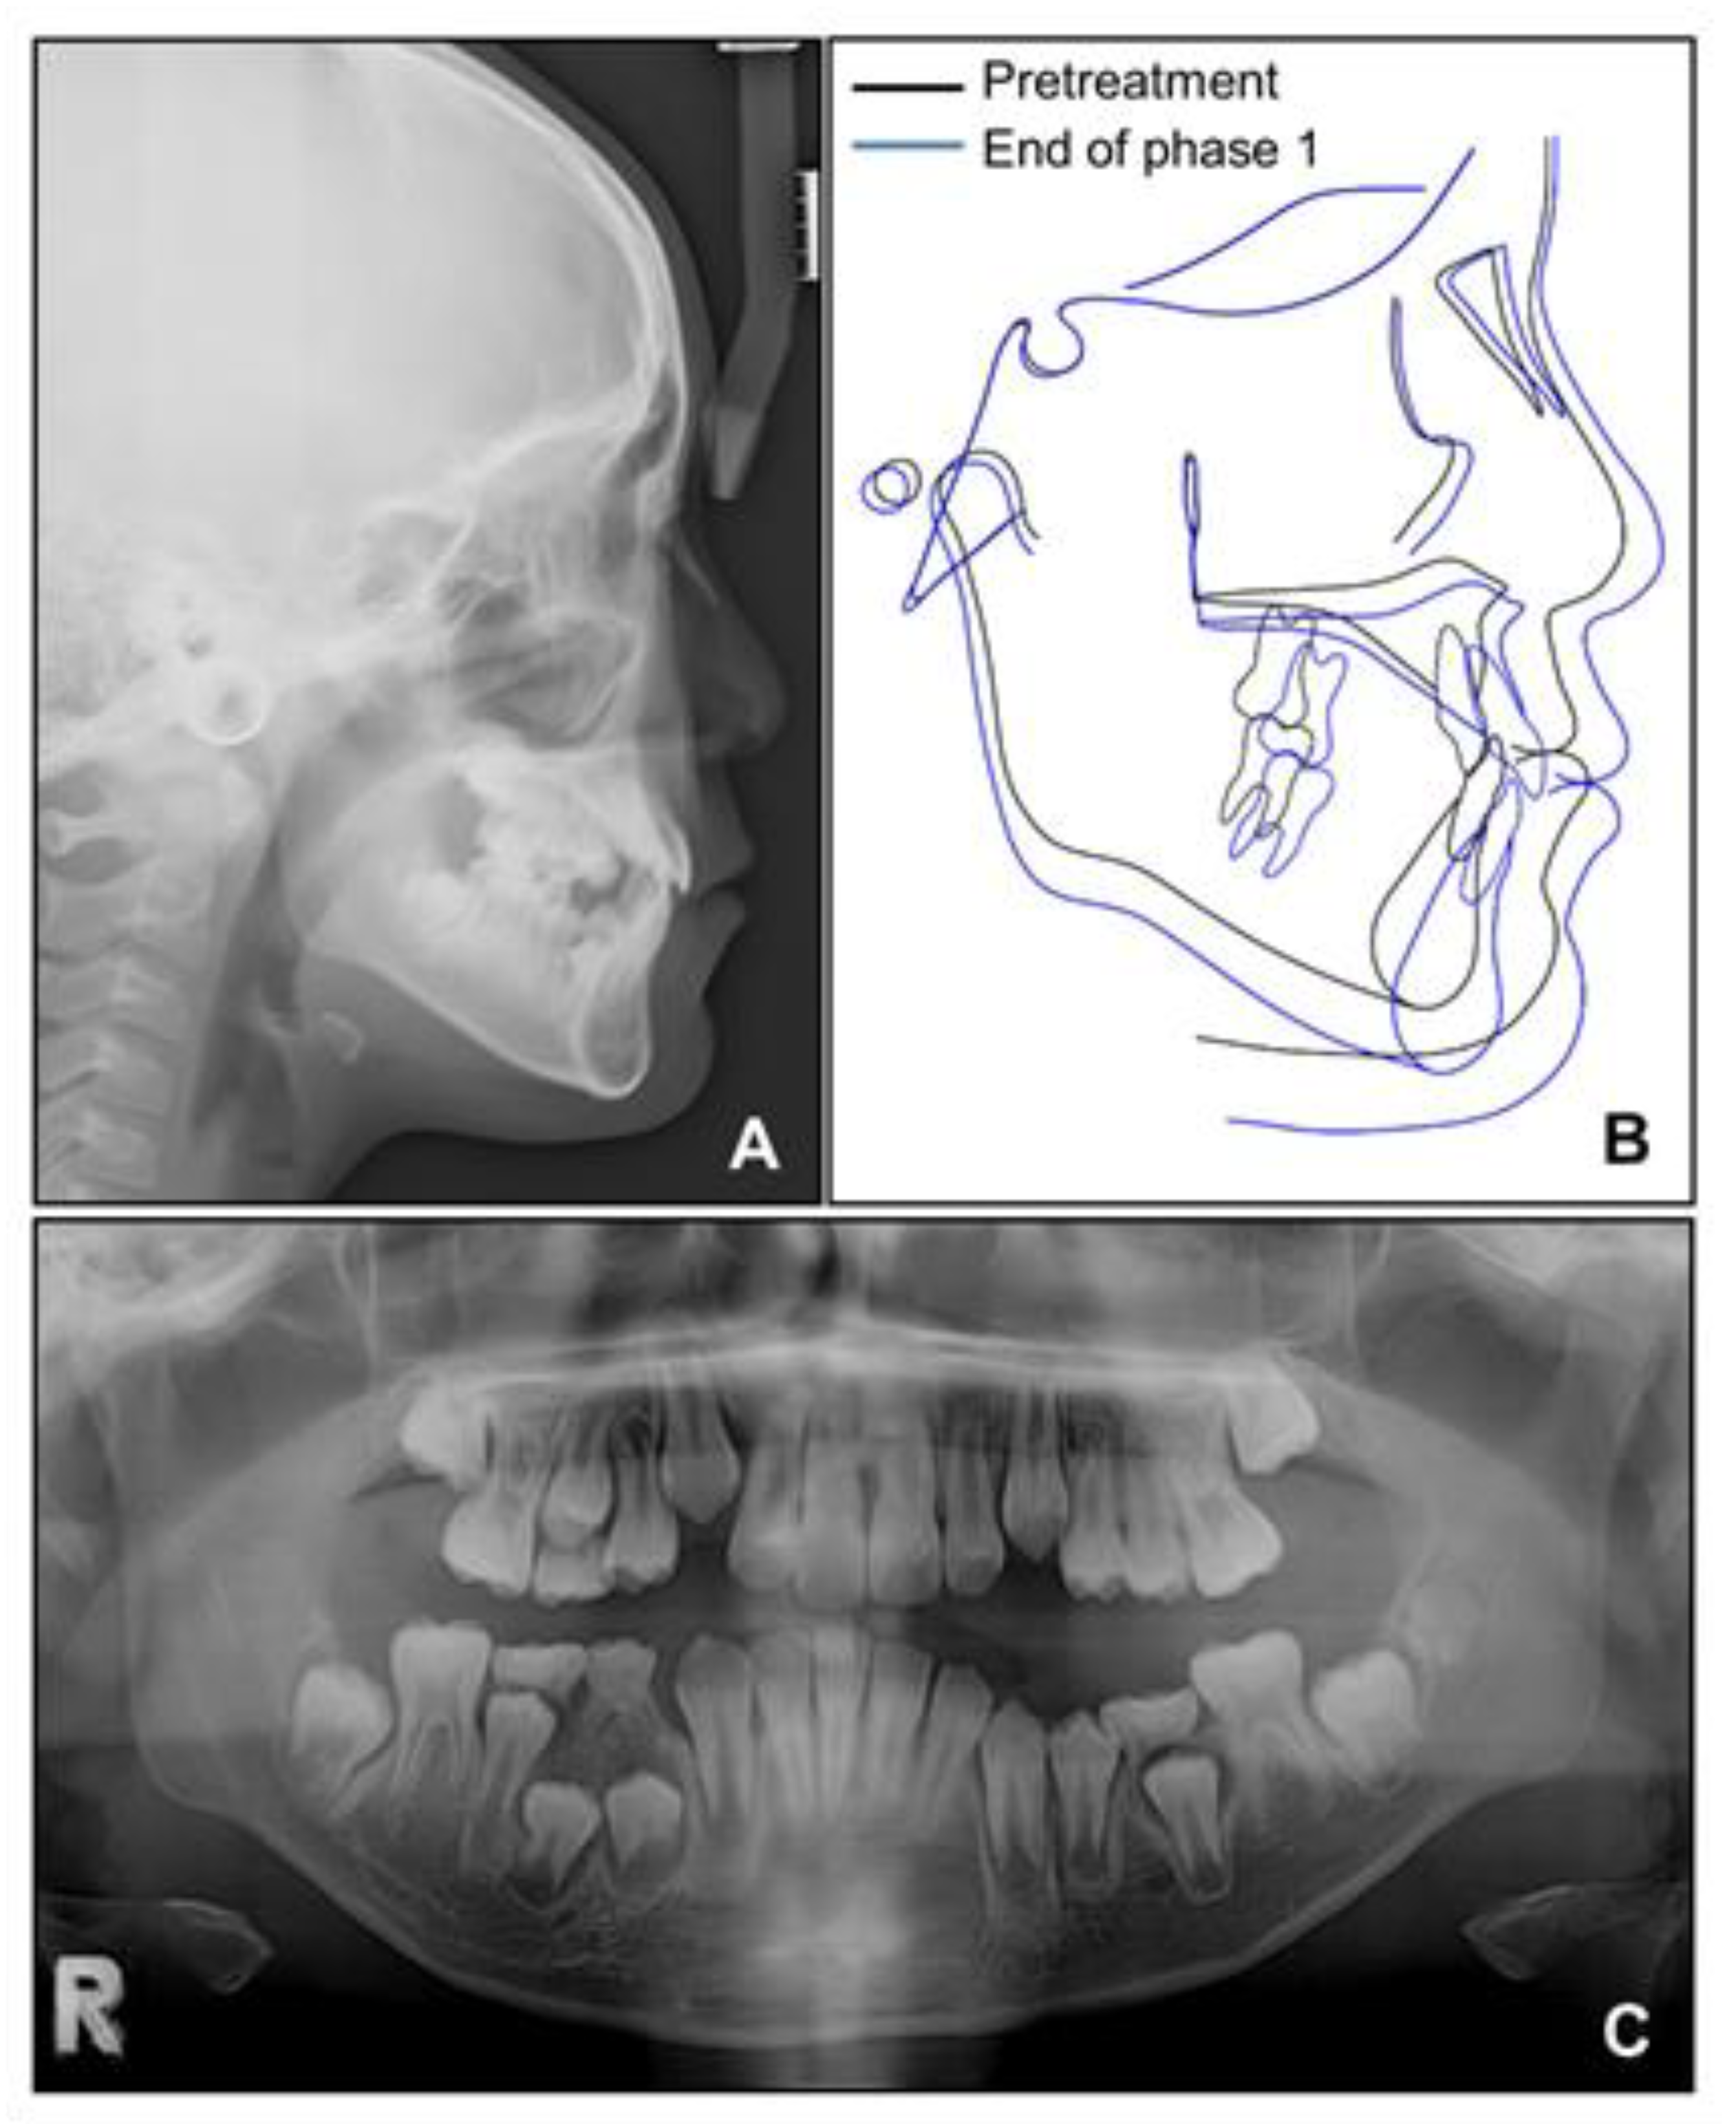

Lateral cephalometric analysis showed an angle of the lines connecting the sella, nasion, and point A (SNA) of 75.4°, an angle of the lines connecting the sella, nasion, and point B (SNB) of 75.7°, and angle of the lines connecting point A, nasion, and point B (ANB) of −0.3° (Table 1 and Figure 3). Both maxillary and mandibular incisors were lingually inclined, and the upper lip was retruded with respect to the Ricketts’ esthetic line. In posteroanterior cephalometric analysis, there were no noticeable asymmetric features. A panoramic radiograph showed that a supernumerary tooth was impacted in the right mandibular premolar area. There were no pathologic osseous findings in the gingival hypertrophic area of the anterior mandible.

Based on this, we decided to start an orthopedic treatment and closely follow up the hypertrophic region. We placed a bonded rapid palatal expansion appliance with a hook for the face mask, and the screw was turned once a day for 2 weeks. The separation of the midpalatal suture was confirmed, and the face mask was set up with the instruction of wearing it for at least 14 h a day. After 5 months, the crossbite was relieved, and the anteroposterior jaw relationship was improved. Nevertheless, there was still a lack of space for the eruption of permanent teeth on the maxillary dentition (Figure 4A). We stopped the use of the face mask and set up an active removable appliance on the maxilla to gain space. After 18 months, sufficient space was made on the maxillary dentition, and we decided to finish the phase 1 treatment (Figure 4B and Figure 5).

Figure 5. Radiographs after phase 1 treatment. (A) Lateral cephalogram; (B) Superimposition before and after phase 1 treatment; (C) Panoramic radiograph.

Cephalometric analysis showed that a skeletal Class I relationship was well-maintained after the phase 1 treatment, with an ANB of 2.5°. Both previously lingually inclined maxillary and mandibular incisors were improved to the normal range. The patient was satisfied with the results and remained stable for 1 year after debonding. While a slight relapse pattern of open bite was observed in the left anterior region, no remarkable increase in the right mandibular right hypertrophic region was observed (Figure 13 and Figure 14).